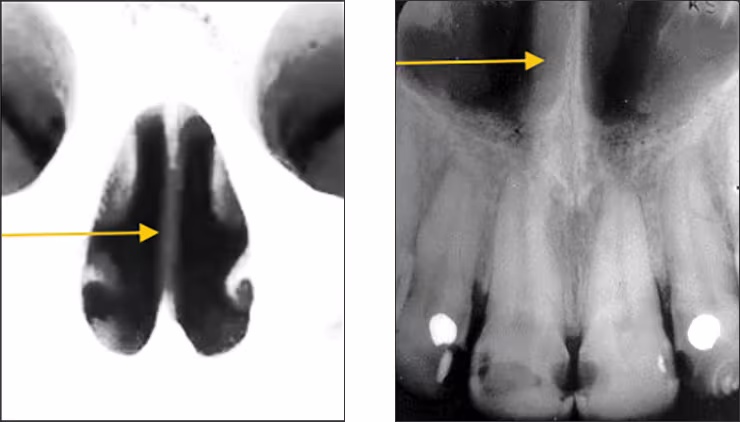

Inferior nasal concha – The inferior nasal concha or turbinate bone projects into the inferior aspect of the nasal fossa from the lateral walls of the nasal cavity (Figures 8 A&B). These bilateral radiopaque structures (conchae) are visible occasionally on central and lateral incisor periapical images.

Figures 8 A&B: Nasal Conchae